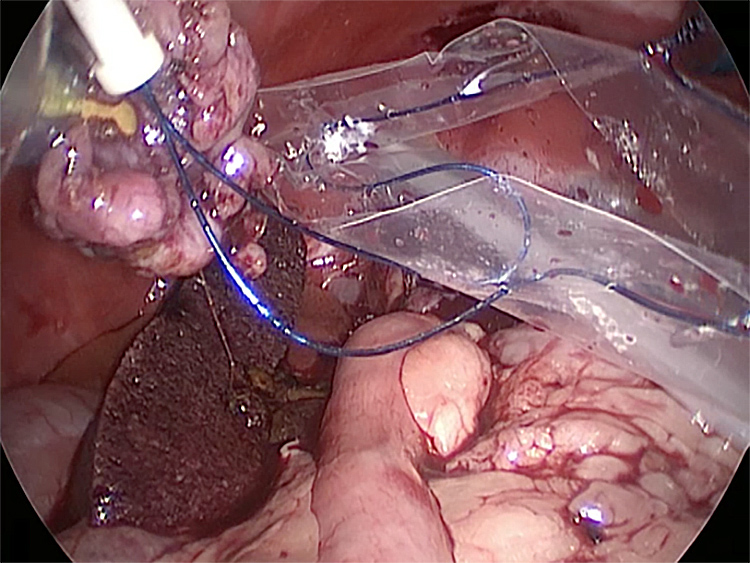

胆嚢の周囲の脂肪や膵臓、十二指腸が激しく癒着し剥離が困難な状態でした。胆嚢は全く確認することができませんでした。

少しずつ癒着を剥がして胆嚢が確認できるようになってきました。 こんなに癒着していることはあまりないので過去に膵炎や胆嚢炎を起こし苦しい時期があったことが推測されました。 それにしてもなかなか胆嚢はでてきませんでした。

癒着(矢印)がひどく胆嚢を確認することができませんでした。 このように癒着しているときはギリギリで剥がすとひどく出血をおこすことがあるので無理にはがそうとしないで、脂肪の血管に注意しながら脂肪ごと剥がしていきます。

胆嚢の頸部に糸を通し動脈を確保しています。